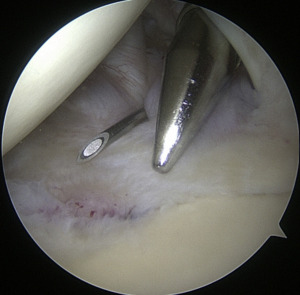

Setup

The coracoid, acromioclavicular joint, clavicle, and acromion are all marked on the skin. If subacromial work is going to be performed, the subacromial bursa may be infiltrated with up to 30 cm3 of a mixture of 0.25% bupivacaine and epinephrine. A standard posterior portal is the typical site of access to the subacromial area and glenohumeral joint. The typical placement of this opening is 2 centimeters medial and 2 centimeters distal to the posterolateral border of the acromion. Palpating the soft tissues of the posterior glenohumeral joint is a common way to confirm the proper position. An anterior portal develops after the joint has been inserted. Figure 4 shows that the surgeon has the option of employing a spinal needle to perform it from the outside in or an inside out approach, depending on his or her choice. The anterosuperior portal is located just off the outside edge of the acromion. You may find the anteroinferior portal directly on the side of the coracoid. One centimeter below the anteroinferior portal is the 5 o’clock portal, which is defined as passing through the subscapularis tendon. Scientists say this entry point is the most common and least invasive as it mimics neurovascular systems. Any anterior portal may be used to conduct basic shoulder arthroscopy. Figure 5 shows the setup of both anterior portals for biceps tenodesis, subscapularis repairs, and labral repairs. For posterior labral repairs, spinal needle localization allows for the creation of an auxiliary posterolateral portal situated immediately distal to the posterolateral limit of the acromion. Anterior positioning of the Wilmington portal, one centimeter laterally to the posterolateral margin of the acromion, is recommended for superior labral repairs. The posterolateral and Wilmington portals are types of trans-rotator cuff tendon access points. Cannulas with the smallest diameters necessary should be used.25

The subacromial region may be accessed via the posterior portal if needed after any intra-articular procedures are finished. Spinal needle localization allows for the creation of a lateral portal, typically 2 cm laterally to the acromion’s lateral border and aligned with the clavicle’s posterior border (Figure 6). For any subacromial surgery, pre-positioned anterior portals may be used (Figure 7). An extra Neviaser portal may be made underneath the spinal needle localization, precisely below the acromioclavicular joint, if that becomes essential. This may be useful for a variety of suture procedures, including those involving the superior labrum, the rotator cuff, and the decompression of the suprascapular nerve (Figure 8).25